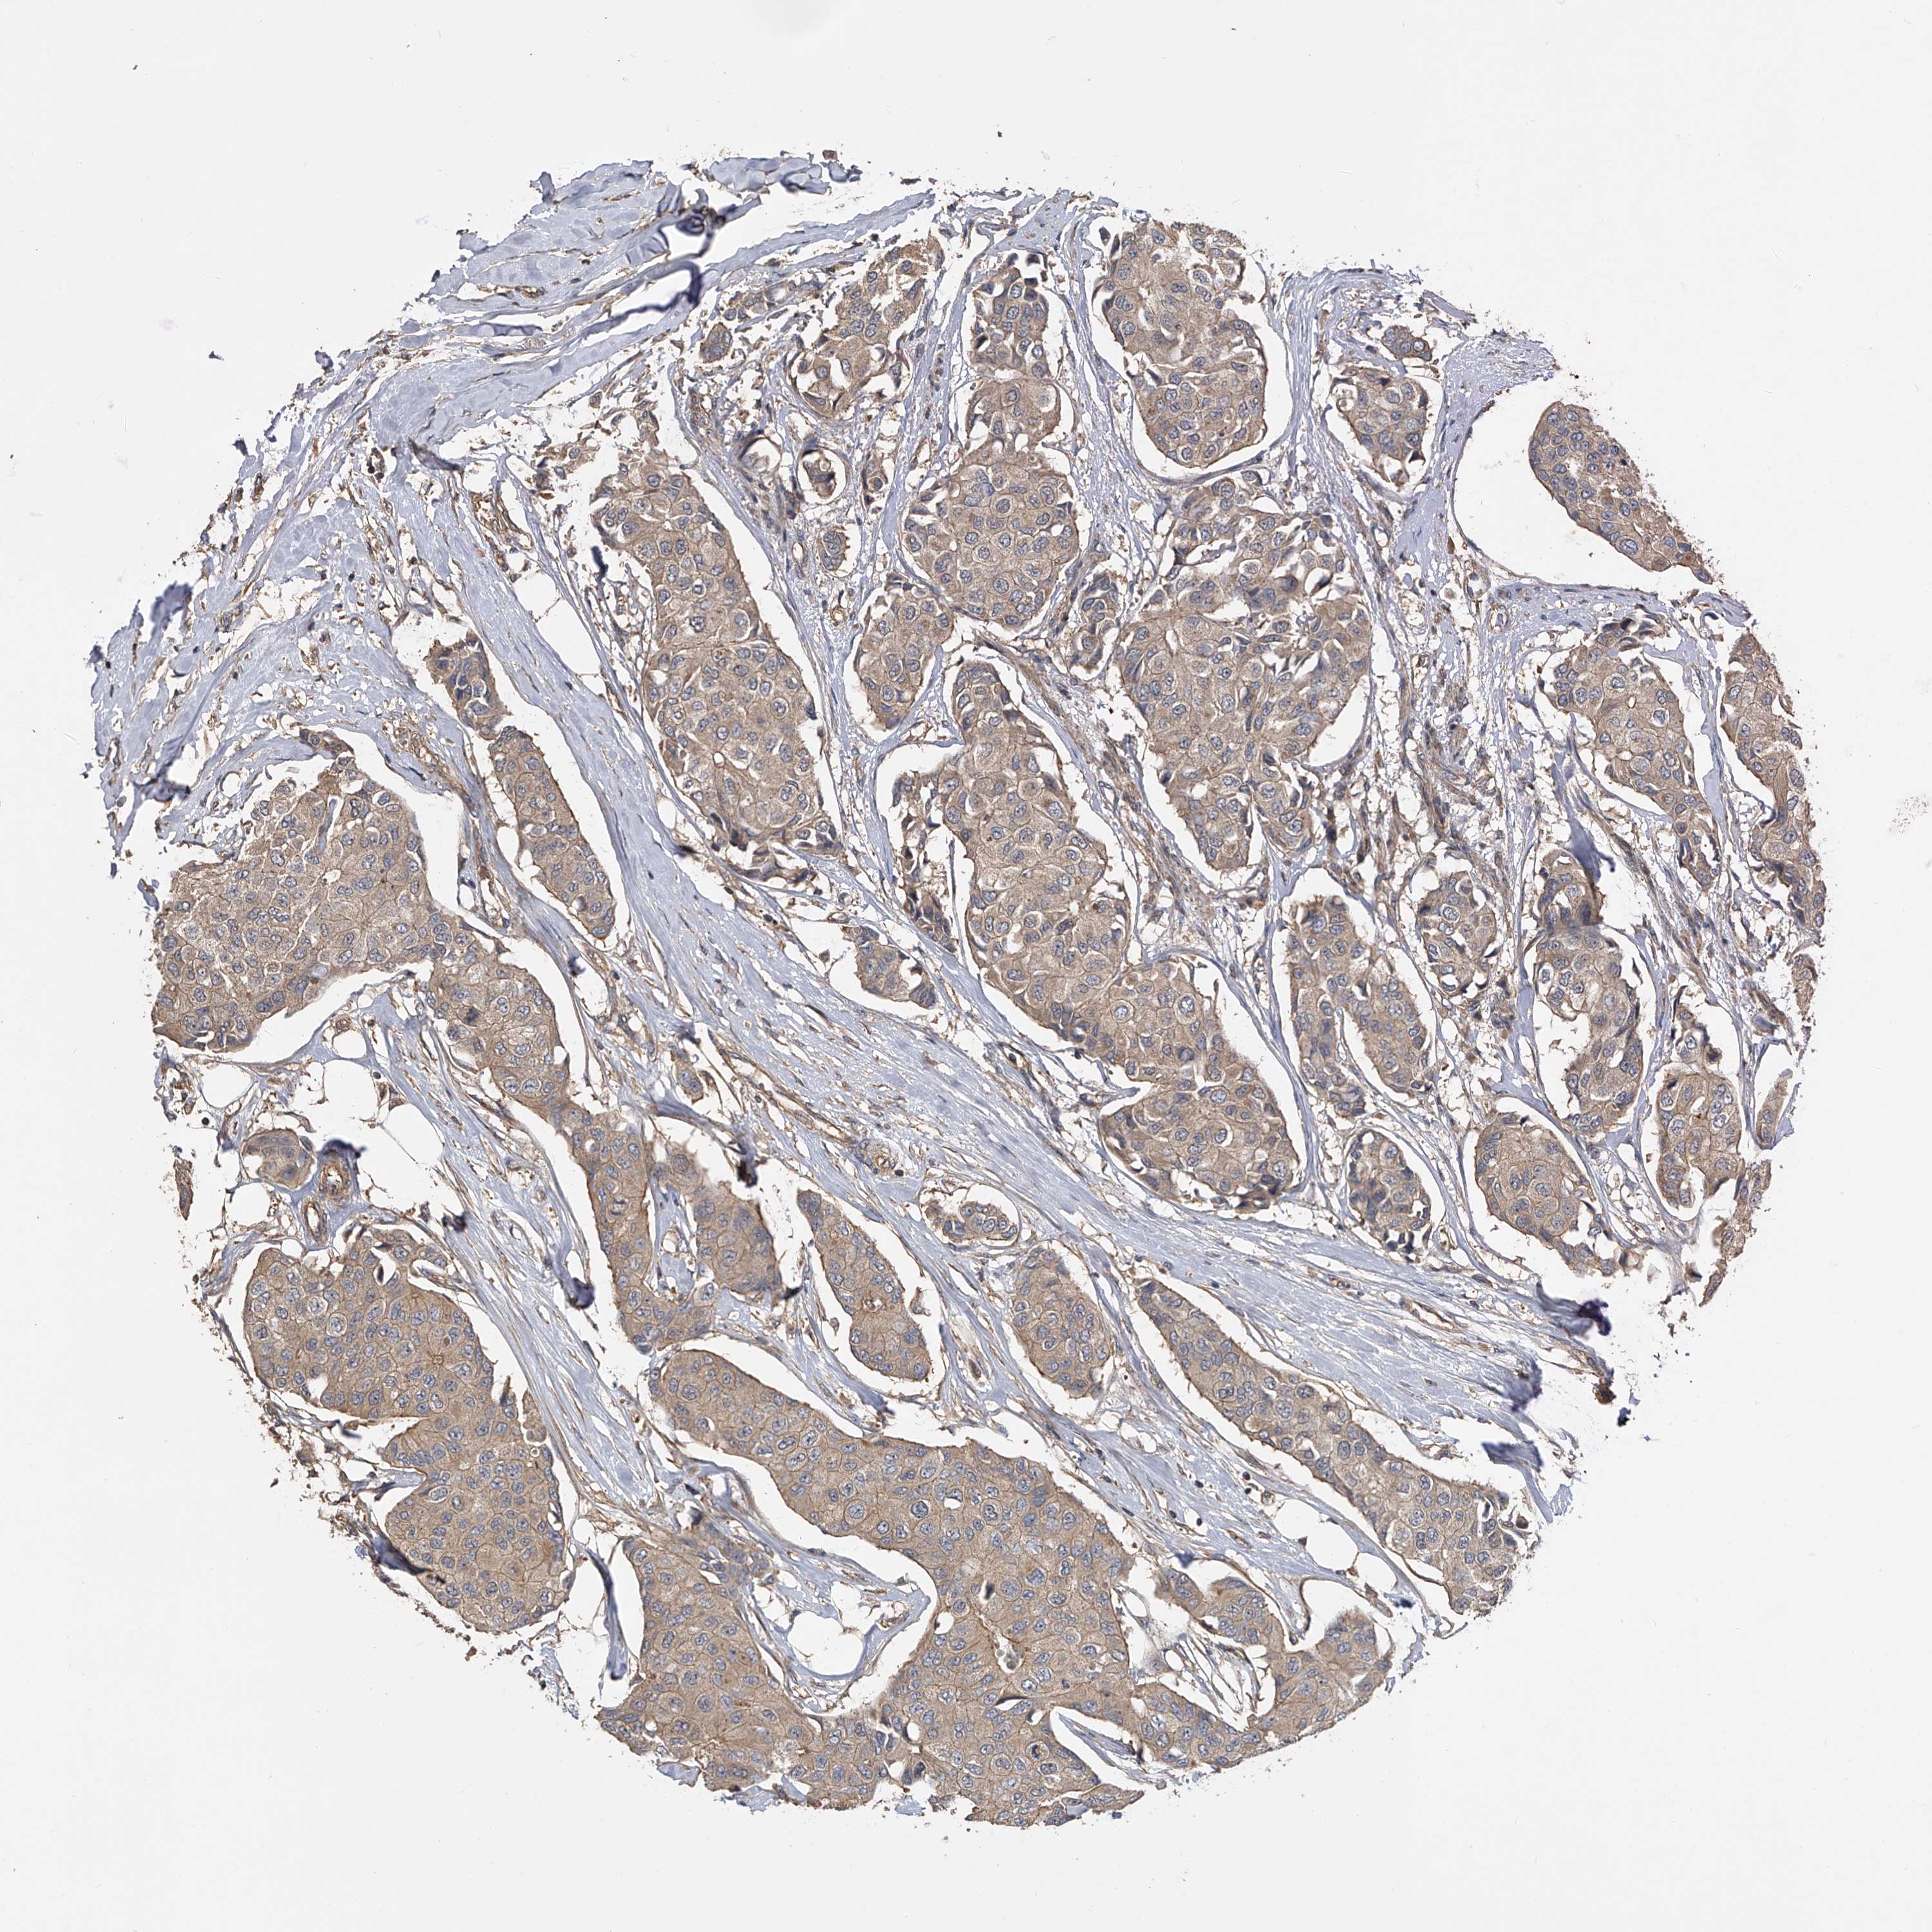

CANCER BREAST CANCER Show tissue menu

BRCA TCGA BRCA VALIDATION PROTEIN EXPRESSION

Breast cancer

Human cancer